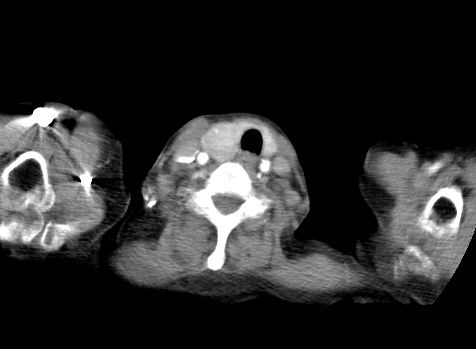

标题: CT23982:女67岁,胸部扫描时发现,甲状腺瘤? [打印本页]

标题: CT23982:女67岁,胸部扫描时发现,甲状腺瘤?

右侧甲状腺腺瘤!支持!不排除甲状腺癌可能!建议手术切除!

右侧甲状腺占位性病变,性质待定(甲状腺腺瘤?);建议:必要时行进一步检查。

右侧甲状腺占位性病变,性质待定(甲状腺腺瘤?);

右侧甲状腺占位性病变,性质待定(甲状腺腺瘤?);建议穿刺活检。

右侧甲状腺占位性病变,甲状腺腺瘤可能,建议穿刺活检。